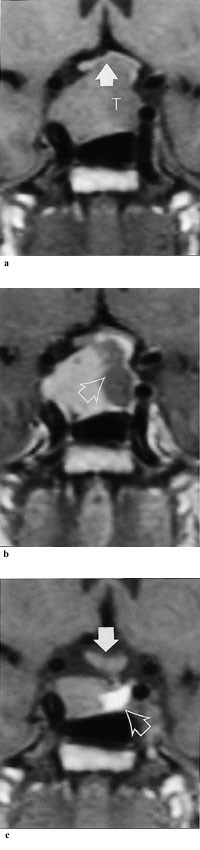

MR-undersøkelse er i dag den beste metoden for påvisning av små hypofyseadenomer (ned til 2 mm). CT-undersøkelse påviser som regel mikroadenomer ( 4 mm) og makroadenomer. Makroadenomer er spesielt viktig å påvise, da disse skal behandles av spesialist i endokrinologi med erfaring i slik behandling (tab 3).

Dopaminagonistene hemmer prolaktinsekresjonen ved å binde seg til og stimulere dopaminreseptorene på de laktotrope cellene (30). Ved langtidsbehandling av mikroprolaktinom gjenopprettes gonadefunksjon hos 80 – 90 % av pasientene (2, 31). Ved tidligere ubehandlet makroprolaktinom oppnås normoprolaktinemi hos inntil 85 % av pasientene (32), og mer enn 25 % reduksjon av tumorvolum sees hos om lag 80 % av pasientene (32, 33) (fig 1).

Kabergolin er også ved makroadenomer et godt førstevalg. I sjeldne tilfeller kan det være nødvendig også å operere pasienten for å redusere lokale trykksymptomer. Hvis man ikke oppnår vesentlig reduksjon av prolaktinnivåene og derfor kan frykte tumorvekst, skal pasientene rutinemessig følges med MR og eventuelt synsfeltsundersøkelse om MR-funn gir grunnlag for det. Det bør imidlertid alltid gjøres en kontrollrøntgenundersøkelse 3 – 6 måneder etter behandlingsstart, avhengig av respons på prolaktinnivået.

Hvis det sees en betydelig reduksjon av prolaktinnivåene og tumor går tilbake, anbefales senere CT- eller MR-kontroller ved stigende prolaktinnivåer eller klinisk mistanke om tumorvekst.